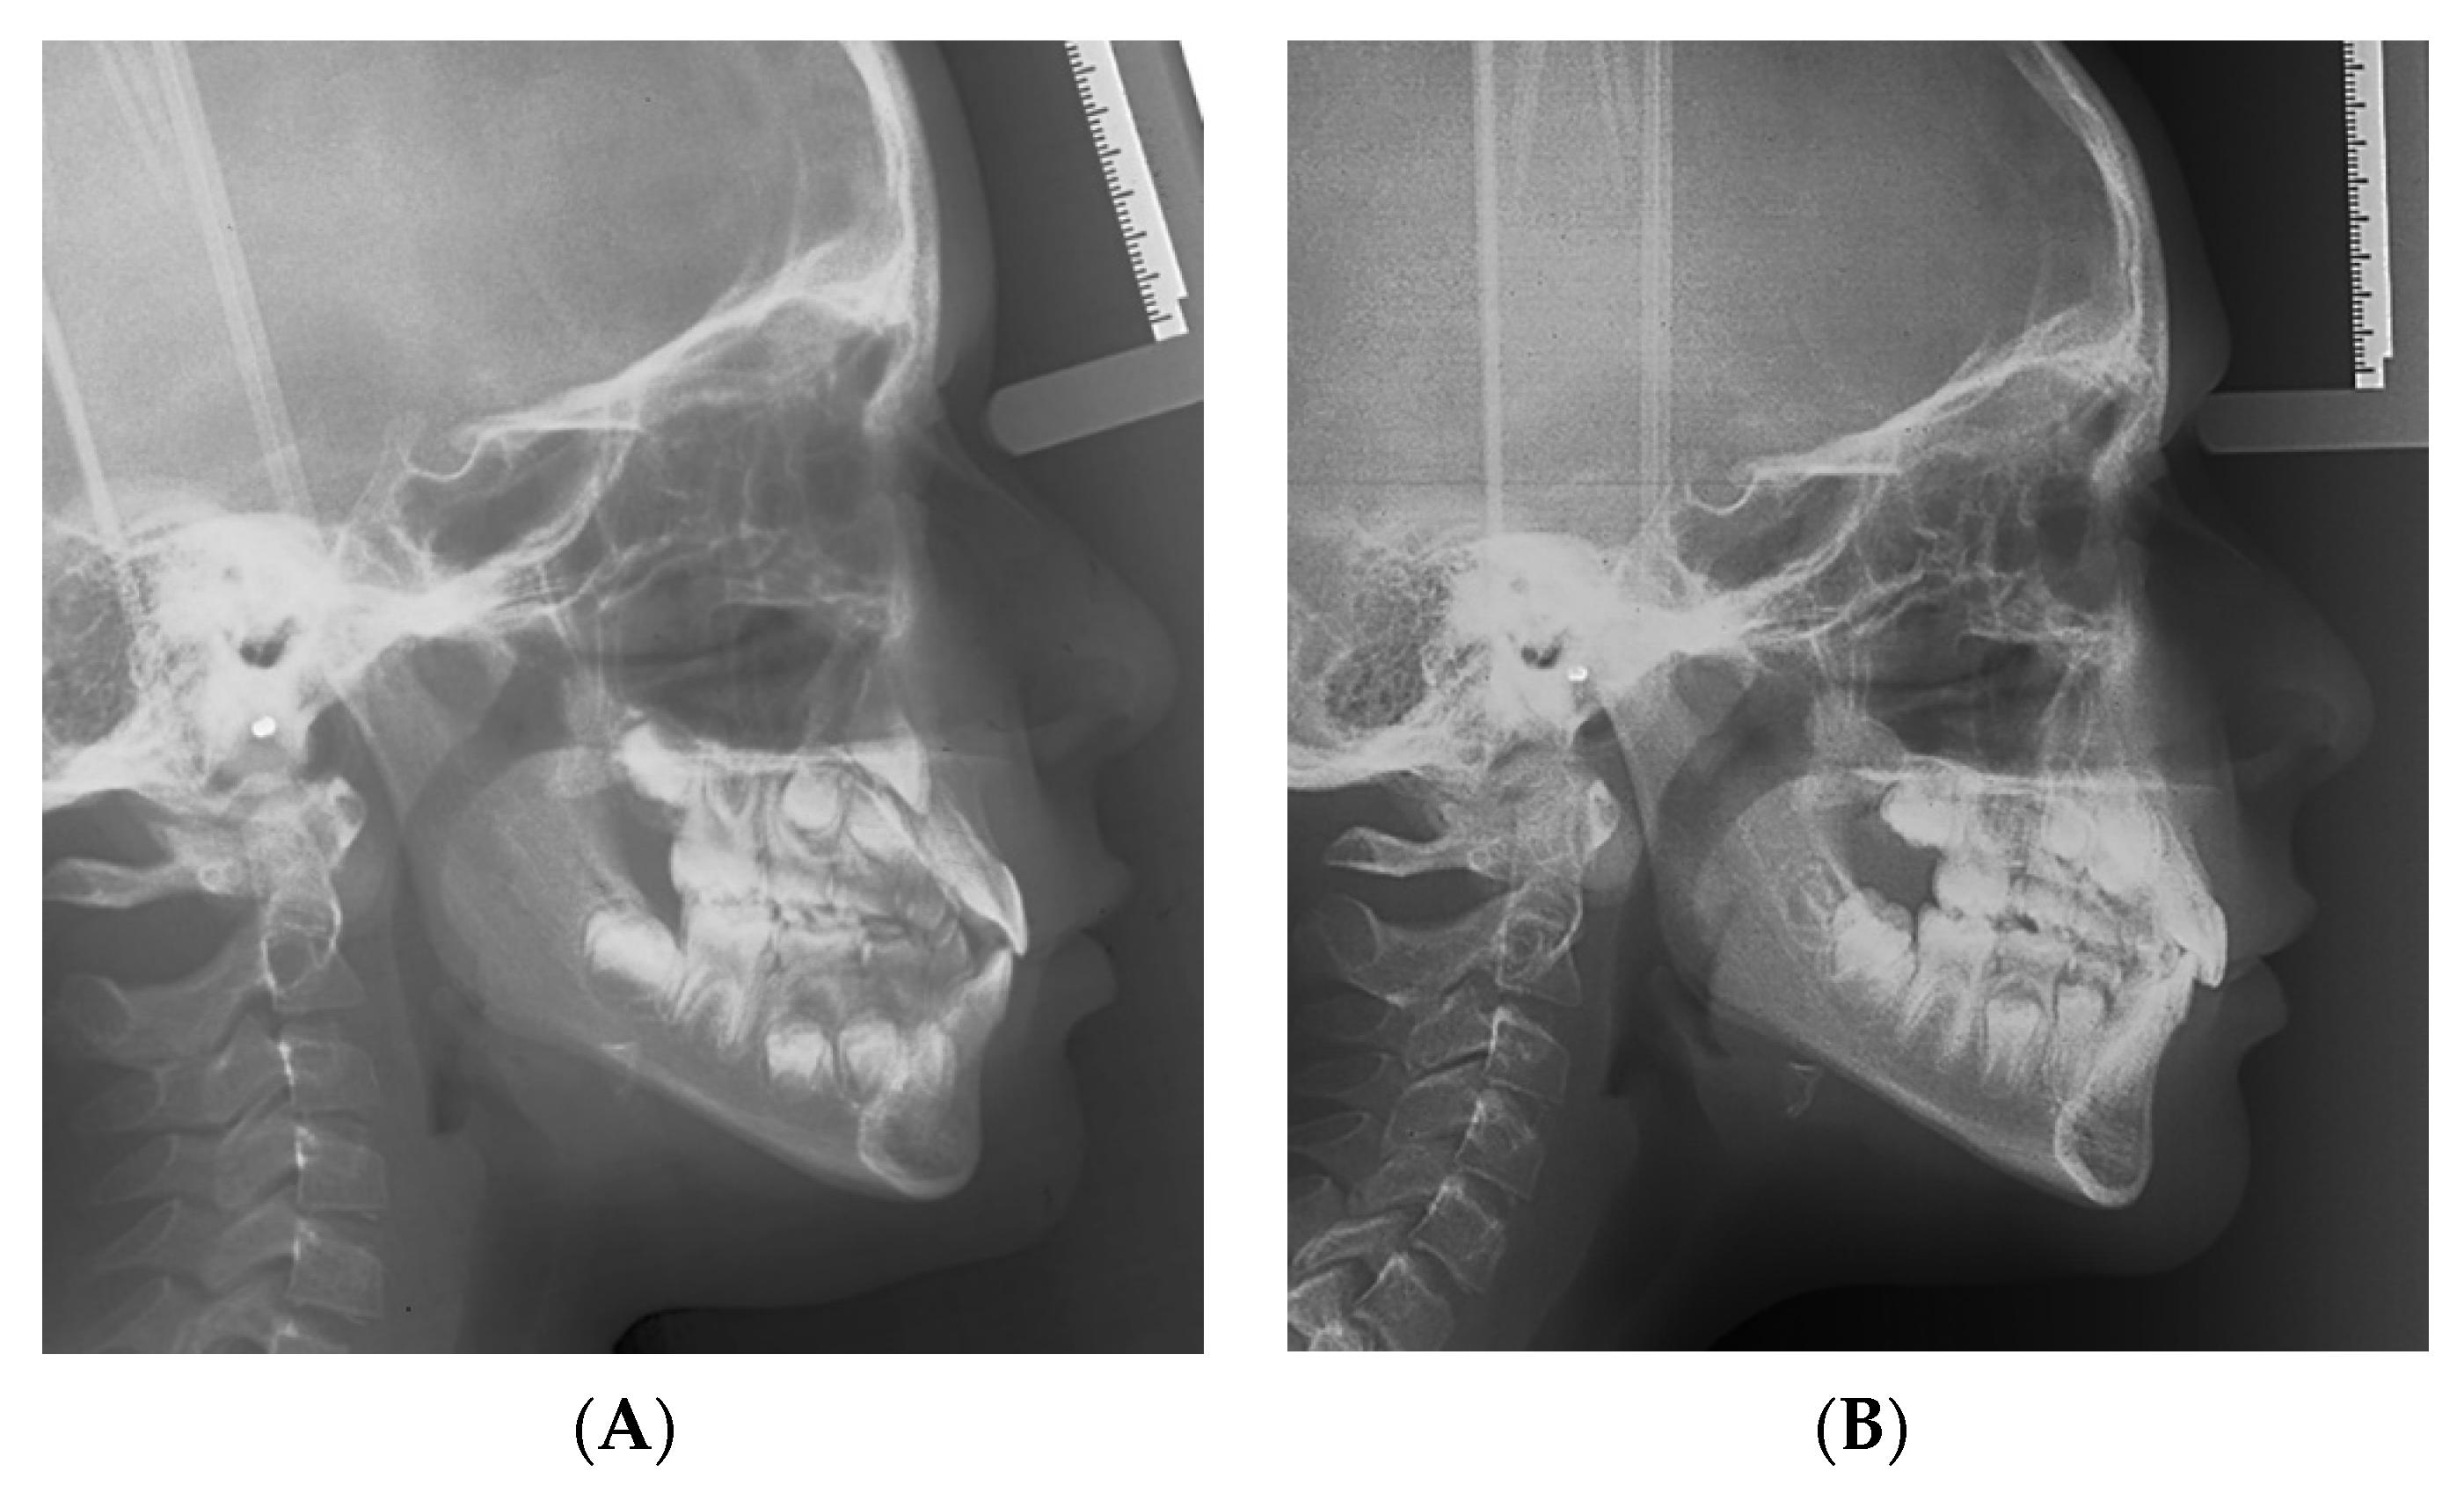

2. Materials and Methods

3. Results

| Variables | Normal Values | Pretreatment | Posttreatment |

|---|---|---|---|

| Angular degrees | |||

| SNA | 82 | 87.7 | 89.6 |

| SNB | 80 | 85.3 | 83.5 |

| ANB | 2 | 2.5 | 6.2 |

| SN to Palatal Plane | 8 | 9.6 | 9.6 |

| SN to Mand. Plane | 32 | 33.3 | 33.5 |

| Co-Go-Me | 125 | 136.1 | 130 |

| Upper Inc. to Palatal Pl | 110 | 119 | 113.6 |

| Lower Inc. to Mand. Pl. | 90 | 87.5 | 91.8 |

| Linear, mm | |||

| Wits | 0 | −6.3 | −3.1 |

| Overjet | 2.5 | 0.4 | 2.7 |

| Overbite | 2.5 | 1.1 | 3.6 |